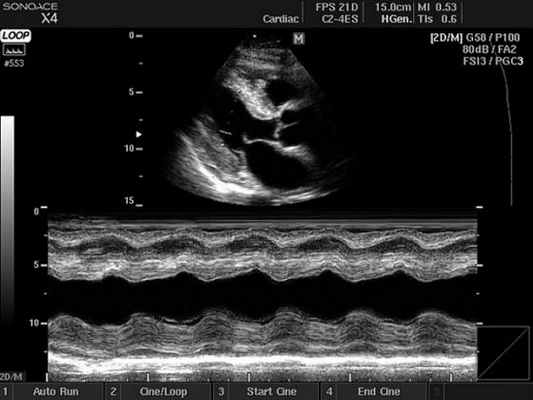

- Двухмерный (2D режим). На монитор выводится изображение сердца в разрезе (в двух измерениях). Данный способ является основным при визуализации этого органа, позволяет детально рассмотреть анатомические отклонения и аномальные движения миокарда, клапанов.

- М-режим (M-mode). Это «усеченный» вариант предыдущего, при котором используется для анализа только одномерное изображение. Основное внимание уделяется одной из линий 2D трассировки, что позволяет более детально исследовать движения створок клапанов и сердечной мышцы.